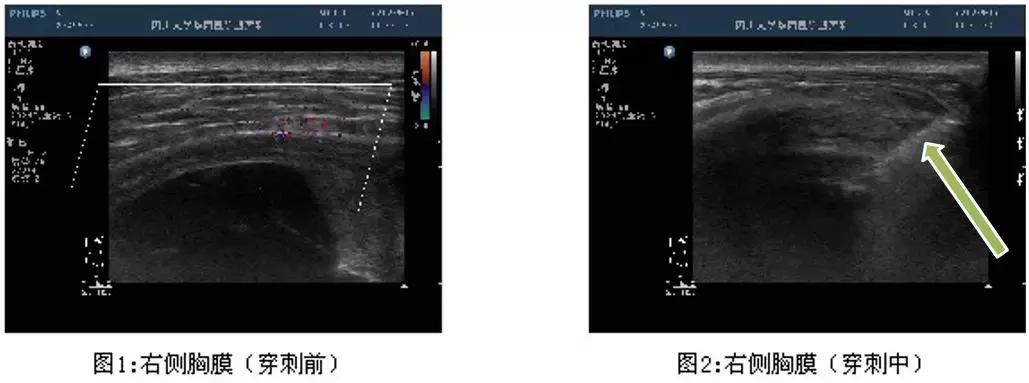

这是在彩超引导下的胸膜活检,胸水较少,胸膜局灶增厚。在穿刺中,可以看到针的所在位置。

优点:实时引导、无射线暴露、费用相对较低。

缺点:依赖超声仪器品质,因为不同的机器达到的效果不同;另外,由于超声扫描的Total的放置角度、位置都对成像有影响,所以超声医师的经验也很重要。